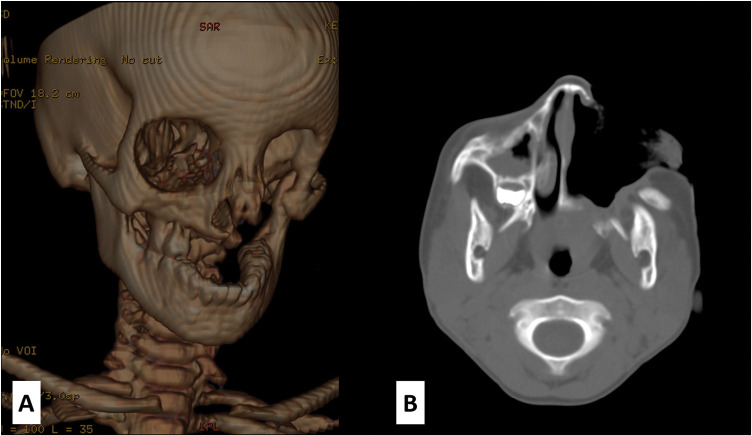

坏疽性坏疽病的瘢痕阶段通常表现为包括硬组织和软组织在内的复合组织损失,导致纤维化,使重建成为一项挑战。当有专业知识时,微血管重建的选择与良好的结果相关。由软组织纤维化或冠状面与颧复合体结合引起的牙关也是常见的表现。有效的治疗需要不同专家团队的参与,并建立明确的治疗目标。本报告报告一例广泛的复合瘤缺损伴咬合,在一个9岁的女性使用局部皮瓣处理。

The scarring stage of noma disease often presents with composite tissue loss involving hard and soft tissues with resultant fibrosis making reconstruction a challenge. Microvascular reconstruction option is associated with good outcomes when the expertise is available. Trismus, which is caused by either soft tissue fibrosis or the union of the coronoid to the zygomatic complex, is also a common presentation. Effective treatment necessitates the involvement of a diverse team of specialists and the establishment of clear treatment objectives. This report presents a case of an extensive composite noma defect with trismus in a 9-year-old female managed using local flaps.